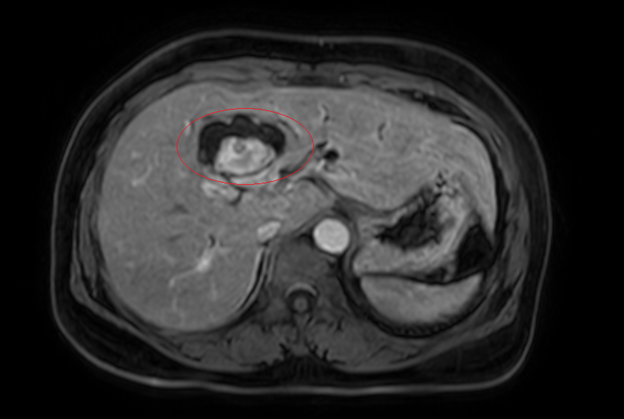

Hình ảnh giãn khu trú đường mật gan trái, tạo cấu trúc dạng nang và sỏi đường mật bên trong (vòng tròn đỏ), chèn ép kèm giãn đường mật trong gan hai bên trên phim chụp MRI

Hình ảnh sỏi đường mật tạo ổ áp xe gan – đường mật gan trái( vòng tròn màu đỏ). Giãn nhẹ đường mật trong gan hai bên. Dày thành nhẹ ngã ba đường mật trên phim chụp cắt lớp vi tính.